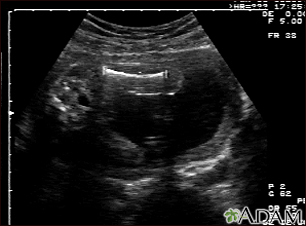

Ultrasound, normal fetus - femur measurement